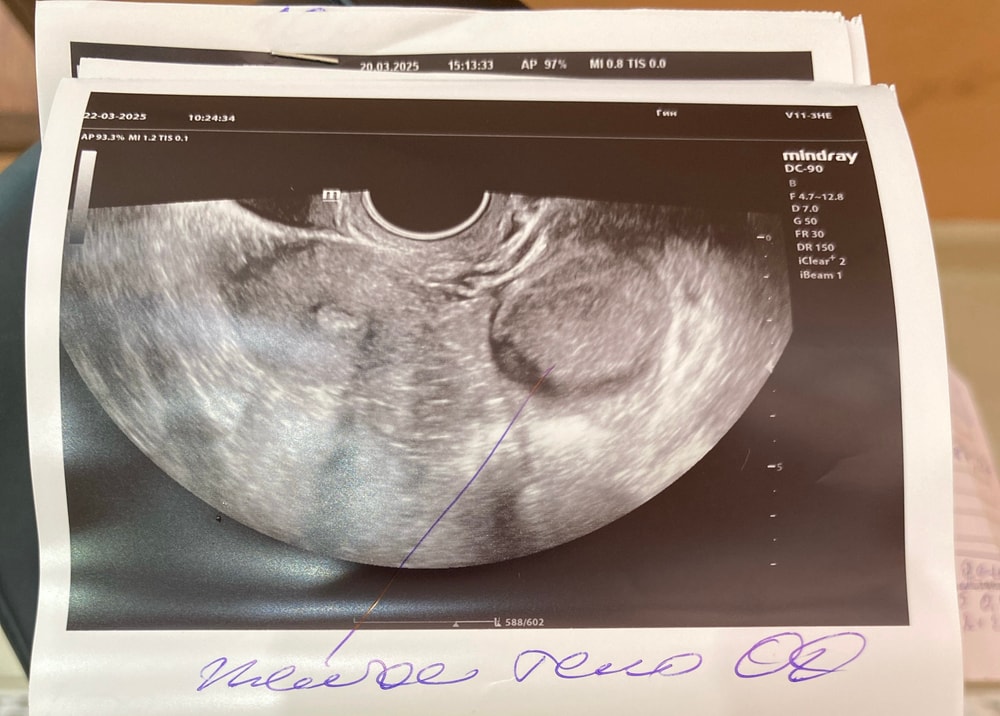

Киста ЖТ или фолликулярная?

На эндометриойдную больше похожа У меня тоже сначала ставили кисту ЖТ, только через 2 месяца поняли, что это эндометриома

Доброе! Киста желтого тела по виду.